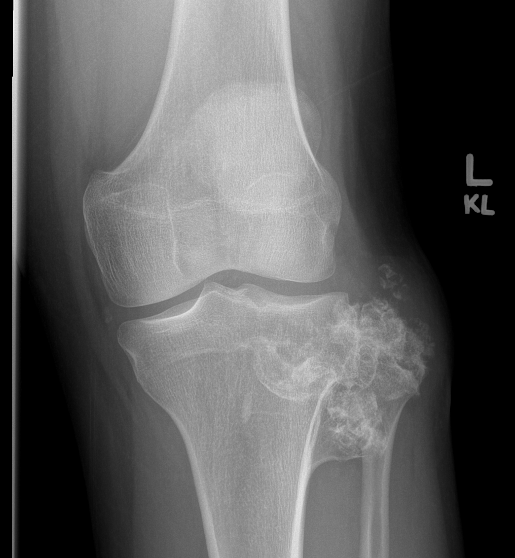

X-ray

Lytic lesion with punctate or spotty calcification

Worrisome features

- growth over time

- large > 5cm

- endosteal scalloping is hallmark of chondrosarcoma